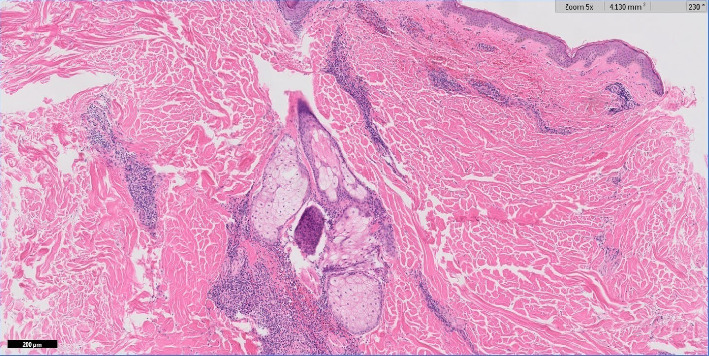

Blastic plasmacytoid dendritic cell neoplasm (BPDCN) is a rare, highly aggressive CD4+ CD56+ hematopoietic malignancy. The cutaneous presentation is variable but often includes violaceous nodules. We present a rare case of BPDCN, which featured dermatological findings consisting of erythematous macules, petechiae, purpura, and a violaceous nodule. A skin biopsy and peripheral blood smear supported a diagnosis of BPDCN. With BPDCN favoring cutaneous involvement, we urge dermatologists to be aware of the possibility of a BPDCN diagnosis in patients who present with purpuric nodules and petechial skin findings, especially when it is not easily explainable by another pathology or medication.